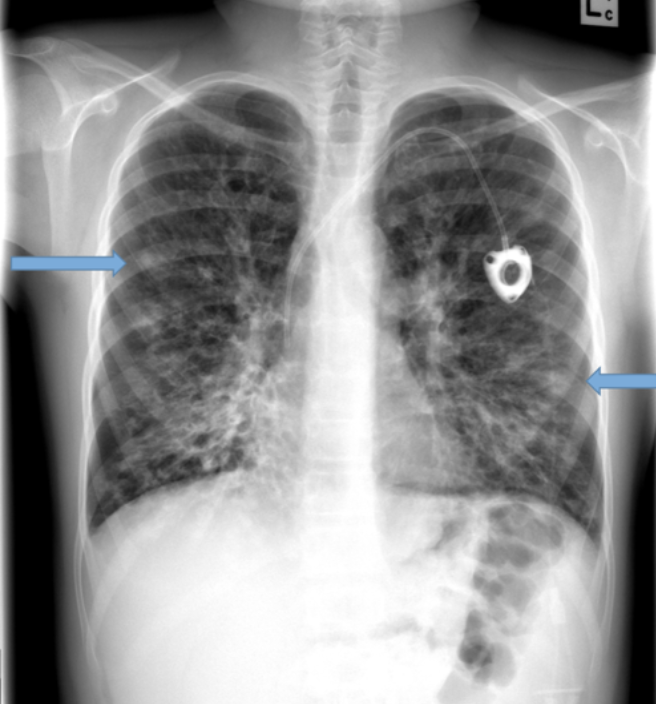

Acute respiratory distress syndrome

- normal heart

-no pleural effusion

-bilateral widespread pulmoonary inflitrates

-air bronchograms